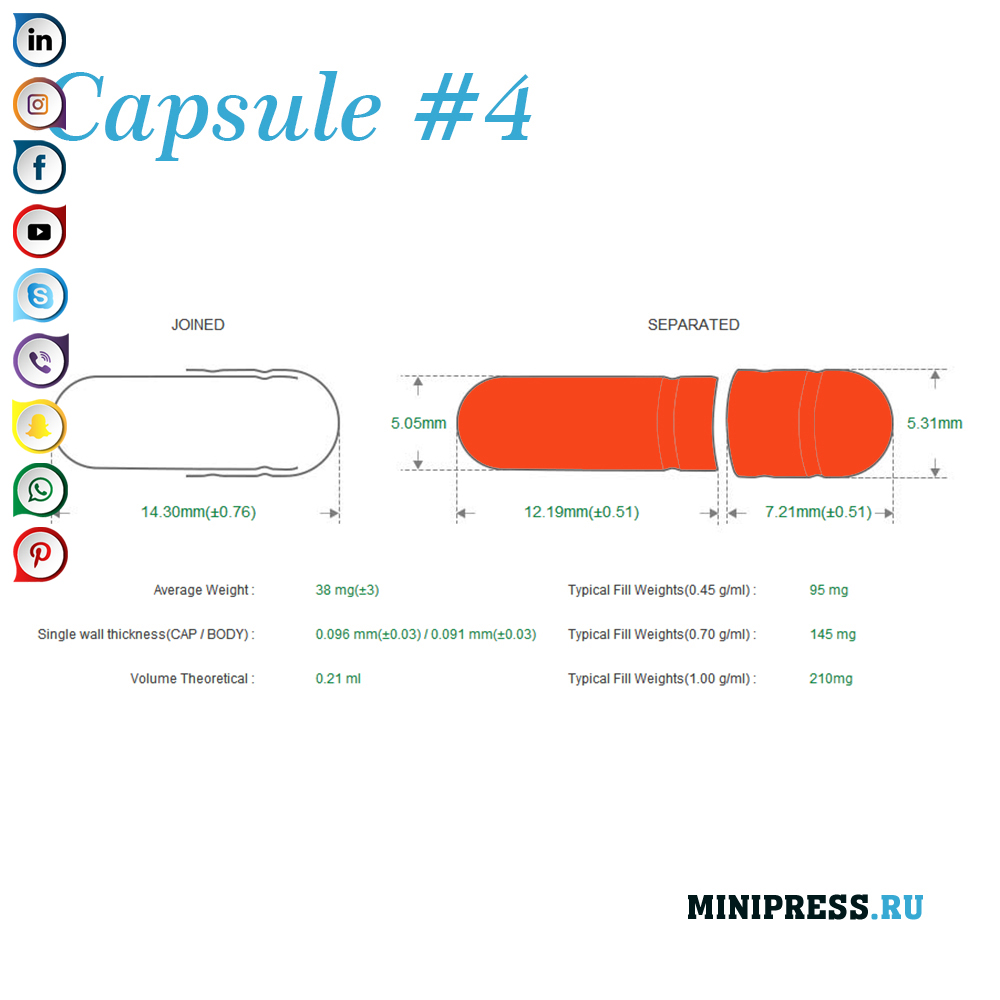

Velike zelatinskih kapsula: 000,00,0,1,2,3,4,5, A, B, C, D, E.